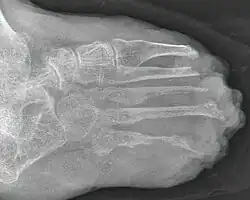

Die lepromatöse Lepra ist die schwerste Form der Krankheit. Durch ungehemmte Vermehrung der Bakterien verbreiten sich diese über Blutbahnen, Nervengewebe, Schleimhäute und das Lymphsystem (mit möglicher Ausbildung einer Elephantiasis)[72] im ganzen Körper. Die Haut ist stark verändert und von Knoten und kleinen Flecken überzogen. Charakteristisch sind die hellroten bis braunen Leprome, die das Gesicht und andere Körperteile zersetzen. Besonders im Gesicht verschmelzen diese zu einem „Löwengesicht“ (Facies leonina). Im weiteren Verlauf kann ein geschwüriger Zerfall mit Befall von Knochen, Muskeln und Sehnen und der inneren Organe erfolgen.